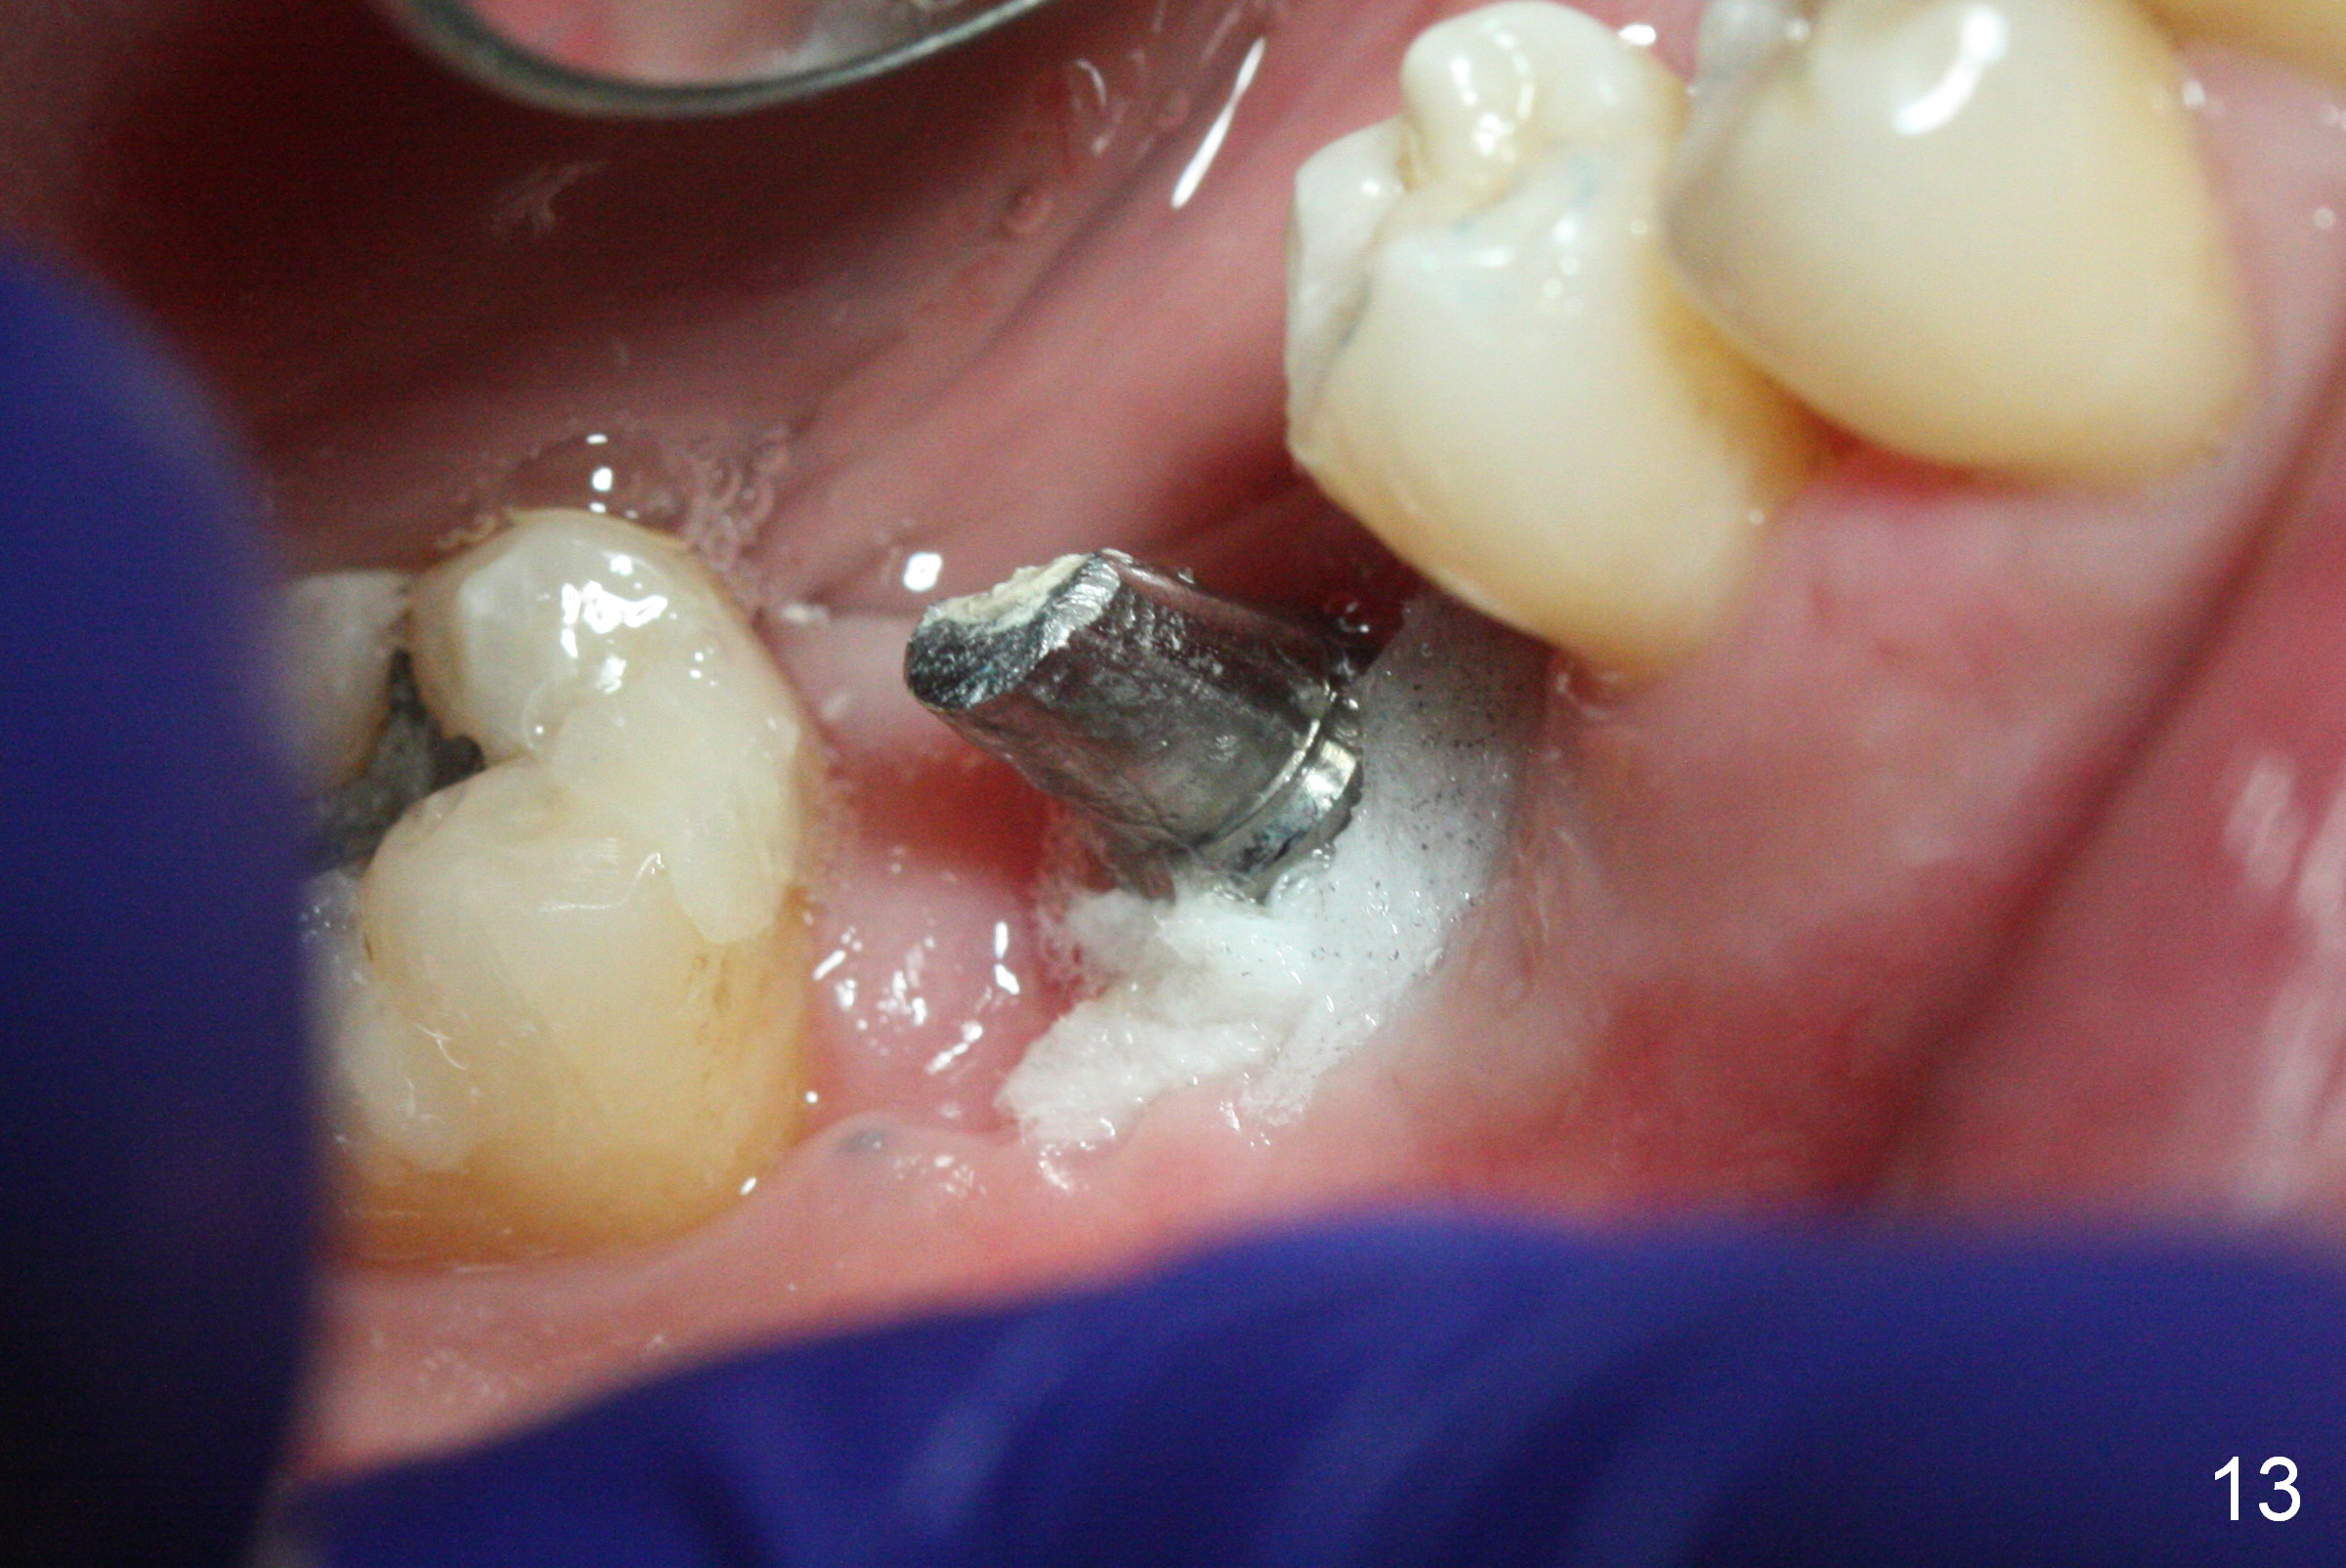

The non-resorbable membrane stays in place 1 month postop (Fig.11 N). When it is removed, the buccal aspect of the cuff of the angled abutment is not covered by bone graft or granulation tissue (Fig.12 C). In fact, the membrane does not hold the bone graft in place as effectively as a provisional. The space is filled with a piece of gauze (Fig.13) while the abutment is reduced for provisional and MO composite at #31 is placed. Before seating the provisional (Fig.14 P), a piece of collagen plug is inserted into the space (*) after removal of the gauze.